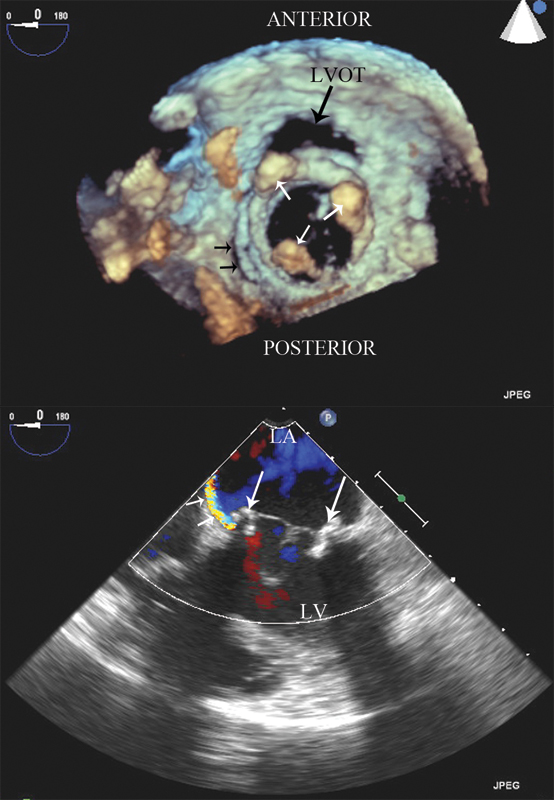

فحوصات تشخيصية لبعض امراض القلب والشرايين التاجية